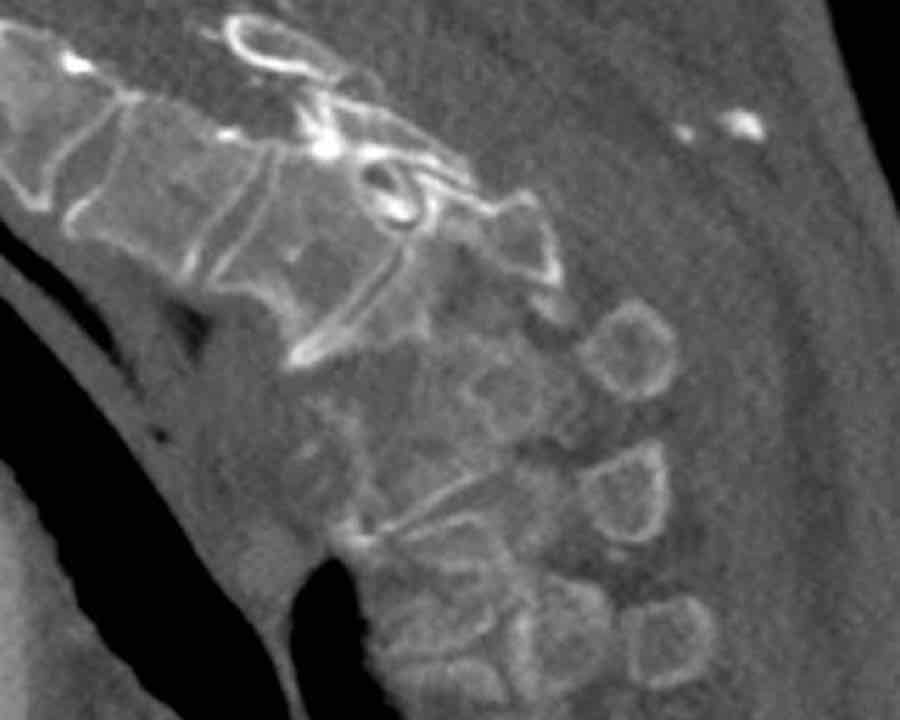

These images are of a 65 year-old woman who fell from her bike.

Scroll through the images.

What are the findings?

What is the highest AO-type of injury?

Findings

There is a type C injury.

In addition to the dislocation in the upper thoracic spine, there is also a sternum fracture, further increasing instability alongside the severe spinal injury.